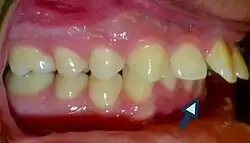

• Falls, which account for 65% of cases (Saber Azami-Aghdash et al., 2015), are the most common etiology for traumatic dental injuries, especially in primary dentition. Trauma to the dentition can occur as a result of sports injuries, cycling accidents, motor vehicle accidents, and physical violence (Peng, 2023).

• Dental carious lesions are a predisposing cause of tooth fractures (Lubisich et al., 2010) due to the already weakened and undermined dental hard tissues.

• Patients with increased overjet or lip incompetence are also at a higher risk of suffering traumatic injuries in the upper incisors (Schatz et al., 2020).

Overjet